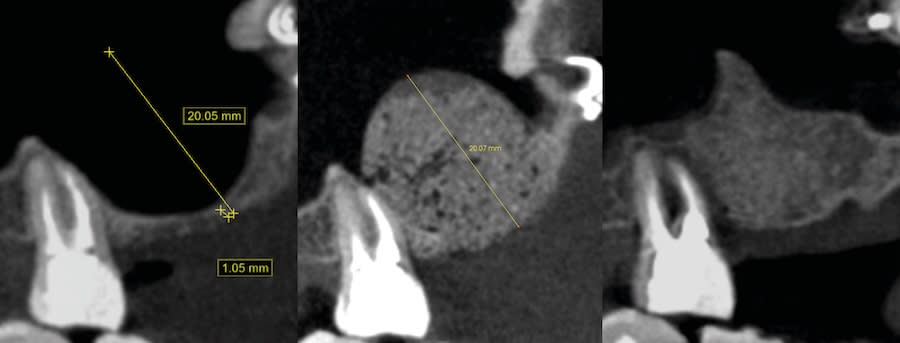

Case 1 (Figure 3 through Figure 24) depicts a 3-year follow-up of combined osseodensification sinus protocol IV in a severely resorbed maxillary ridge with ≤0.5 mm bone height in molar sites and horizontal deficiency at the first premolar site, using a two-stage approach for implant placement.

Case 2 (Figure 25 through Figure 36) illustrates a 3-year follow-up of the osseodensification sinus protocol IV in a severely resorbed right maxillary ridge with <0.5 mm bone height in molar sites, using a two-stage approach for implant placement.

Case 3 (Figure 37 through 44) shows a case of significant trauma history with a 3-year follow-up of the osseodensification sinus protocol IV in a severely resorbed right maxillary ridge with ≤0.5 mm bone height in molar sites, using a two-stage approach for implant placement.